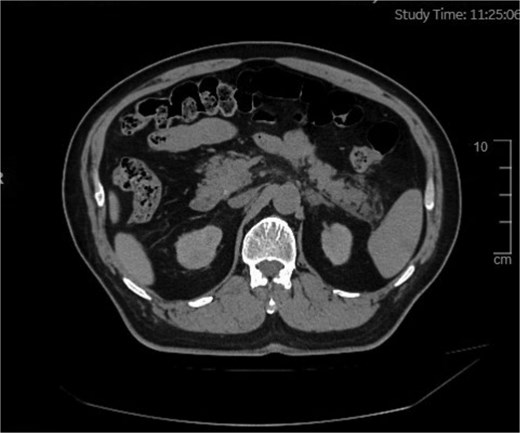

Diagnostic workup included a normal electrocardiogram (sinus rhythm, 68 beats/min), which ruled out a cardiac etiology for the abdominal pain. Abdominal Ultrasound (5 June 2025) revealed findings of fatty liver and multiple hepatic cysts (largest 1.5 cm), postprandial gallbladder (no stones/wall thickening), and unremarkable spleen (noting ultrasound limitations for early pancreatitis). However, ultrasound has inherent limitations for early pancreatitis. Given the clinical suspicion for pancreatitis and the need for cross-sectional imaging while prioritizing patient safety due to the substantial intraoperative contrast load already administered, an abdominal non-contrast computed tomography (NCCT) was purposefully obtained on 5 June 2025. This study confirmed the hepatic cysts and additionally identified bilateral renal cysts (largest 1.2 cm). Crucially, it demonstrated findings consistent with mild-to-moderate AP (Balthazar Grade B), characterized by pancreatic tail exudation without evidence of necrosis or peripancreatic fluid collection (Fig. 1).

Abdominal scan showing an area of exudative changes within the tail of the pancreas (Balthazar grade B).